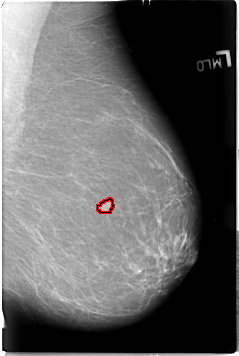

B_3018_1.LEFT_MLO

LEFT_MLO LINES 4624 PIXELS_PER_LINE 3104 BITS_PER_PIXEL 12 RESOLUTION 50 OVERLAY

FILE: B_3018_1.LEFT_MLO.OVERLAY

TOTAL_ABNORMALITIES 1

ABNORMALITY 1

LESION_TYPE MASS SHAPE LOBULATED MARGINS ILL_DEFINED

ASSESSMENT 4

SUBTLETY 4

PATHOLOGY MALIGNANT

TOTAL_OUTLINES 1

BOUNDARY